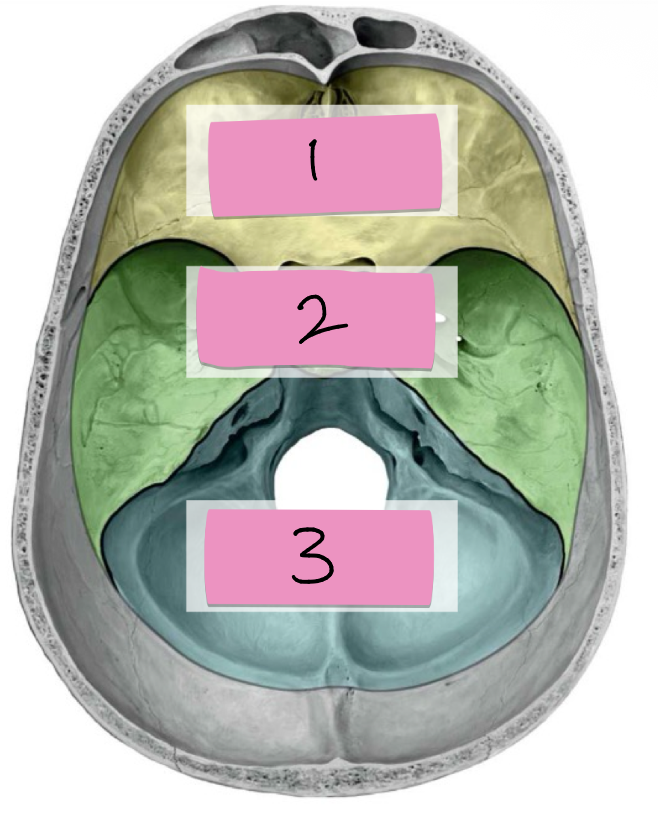

Name 1 and what bone part of this region:

Anterior cranial fossa:

2 Frontal bone

Ethmoid

Name 2 and what bone part of this region:

Middle cranial fossa:

Sphenoid (2)

Temporal (2)

Name 3 and what bone part of this region:

Posterior Cranial Fossa: